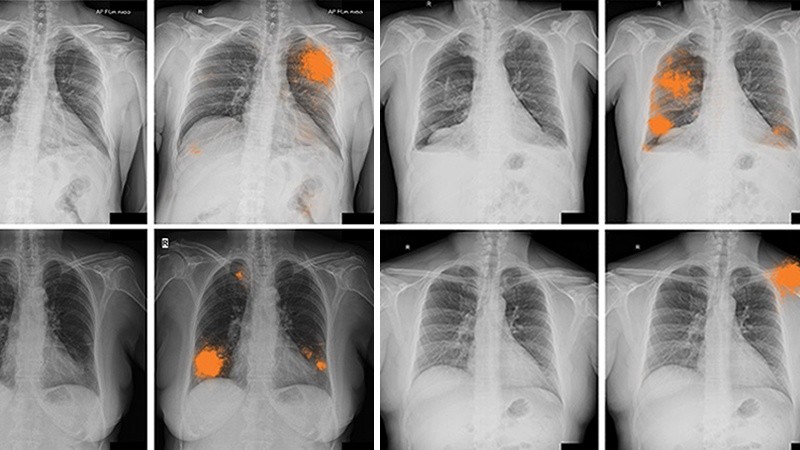

La interpretación de imágenes es tal vez una de las aplicaciones más maduras y visibles de la IA en la medicina. Los algoritmos de aprendizaje profundo, una rama más avanzada del aprendizaje automático, ya demostraron que pueden analizar radiografías, tomografías computarizadas, resonancias magnéticas y hasta muestras de tejido con una velocidad y precisión superiores a los procedimientos tradicionales, llegando incluso hasta elaborar informes detallados.

Un estudio publicado en junio de 2025 mostró cómo la incorporación de inteligencia artificial generativa en tiempo real dentro del sistema de imágenes permitió que los informes se redactaran automáticamente mientras el radiólogo analizaba los estudios, produciendo un borrador que luego era revisado por el especialista. Esta integración no solo mantuvo la calidad del diagnóstico, sino que además redujo drásticamente los tiempos de trabajo, con mejoras en la eficiencia que llegaron hasta el 40%. Además, esta herramienta incluye funciones de triaje automatizado, de modo que si el sistema detecta una condición grave, la marca y la compara con el historial del paciente para alertar al radiólogo de inmediato, incluso antes de que este haya revisado las imágenes.